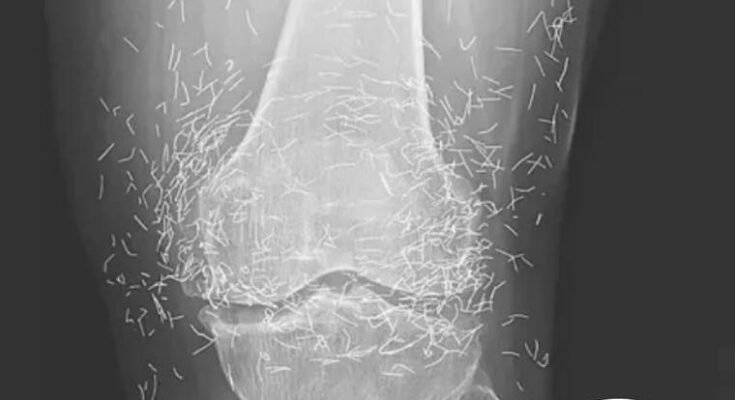

The X-ray images published in the New England Journal of Medicine showed dozens—possibly hundreds—of fine gold needles clustered around both knees. Some were deeply embedded in muscle tissue, while others rested just under the skin.

While gold is a non-reactive metal, the problem lies in the body’s defensive response. Over time, even inert materials can trigger inflammation as the immune system attempts to isolate the foreign objects. In severe cases, this leads to abscess formation or tissue hardening, both of which can worsen mobility and pain.

Another concern, Guermazi added, is that metallic fragments in the body can interfere with medical imaging. “Needles like these can distort X-rays or CT scans,” he said. “And MRIs are out of the question. The magnetic force could cause the metal to shift, potentially puncturing tissue or blood vessels. It’s extremely dangerous.”